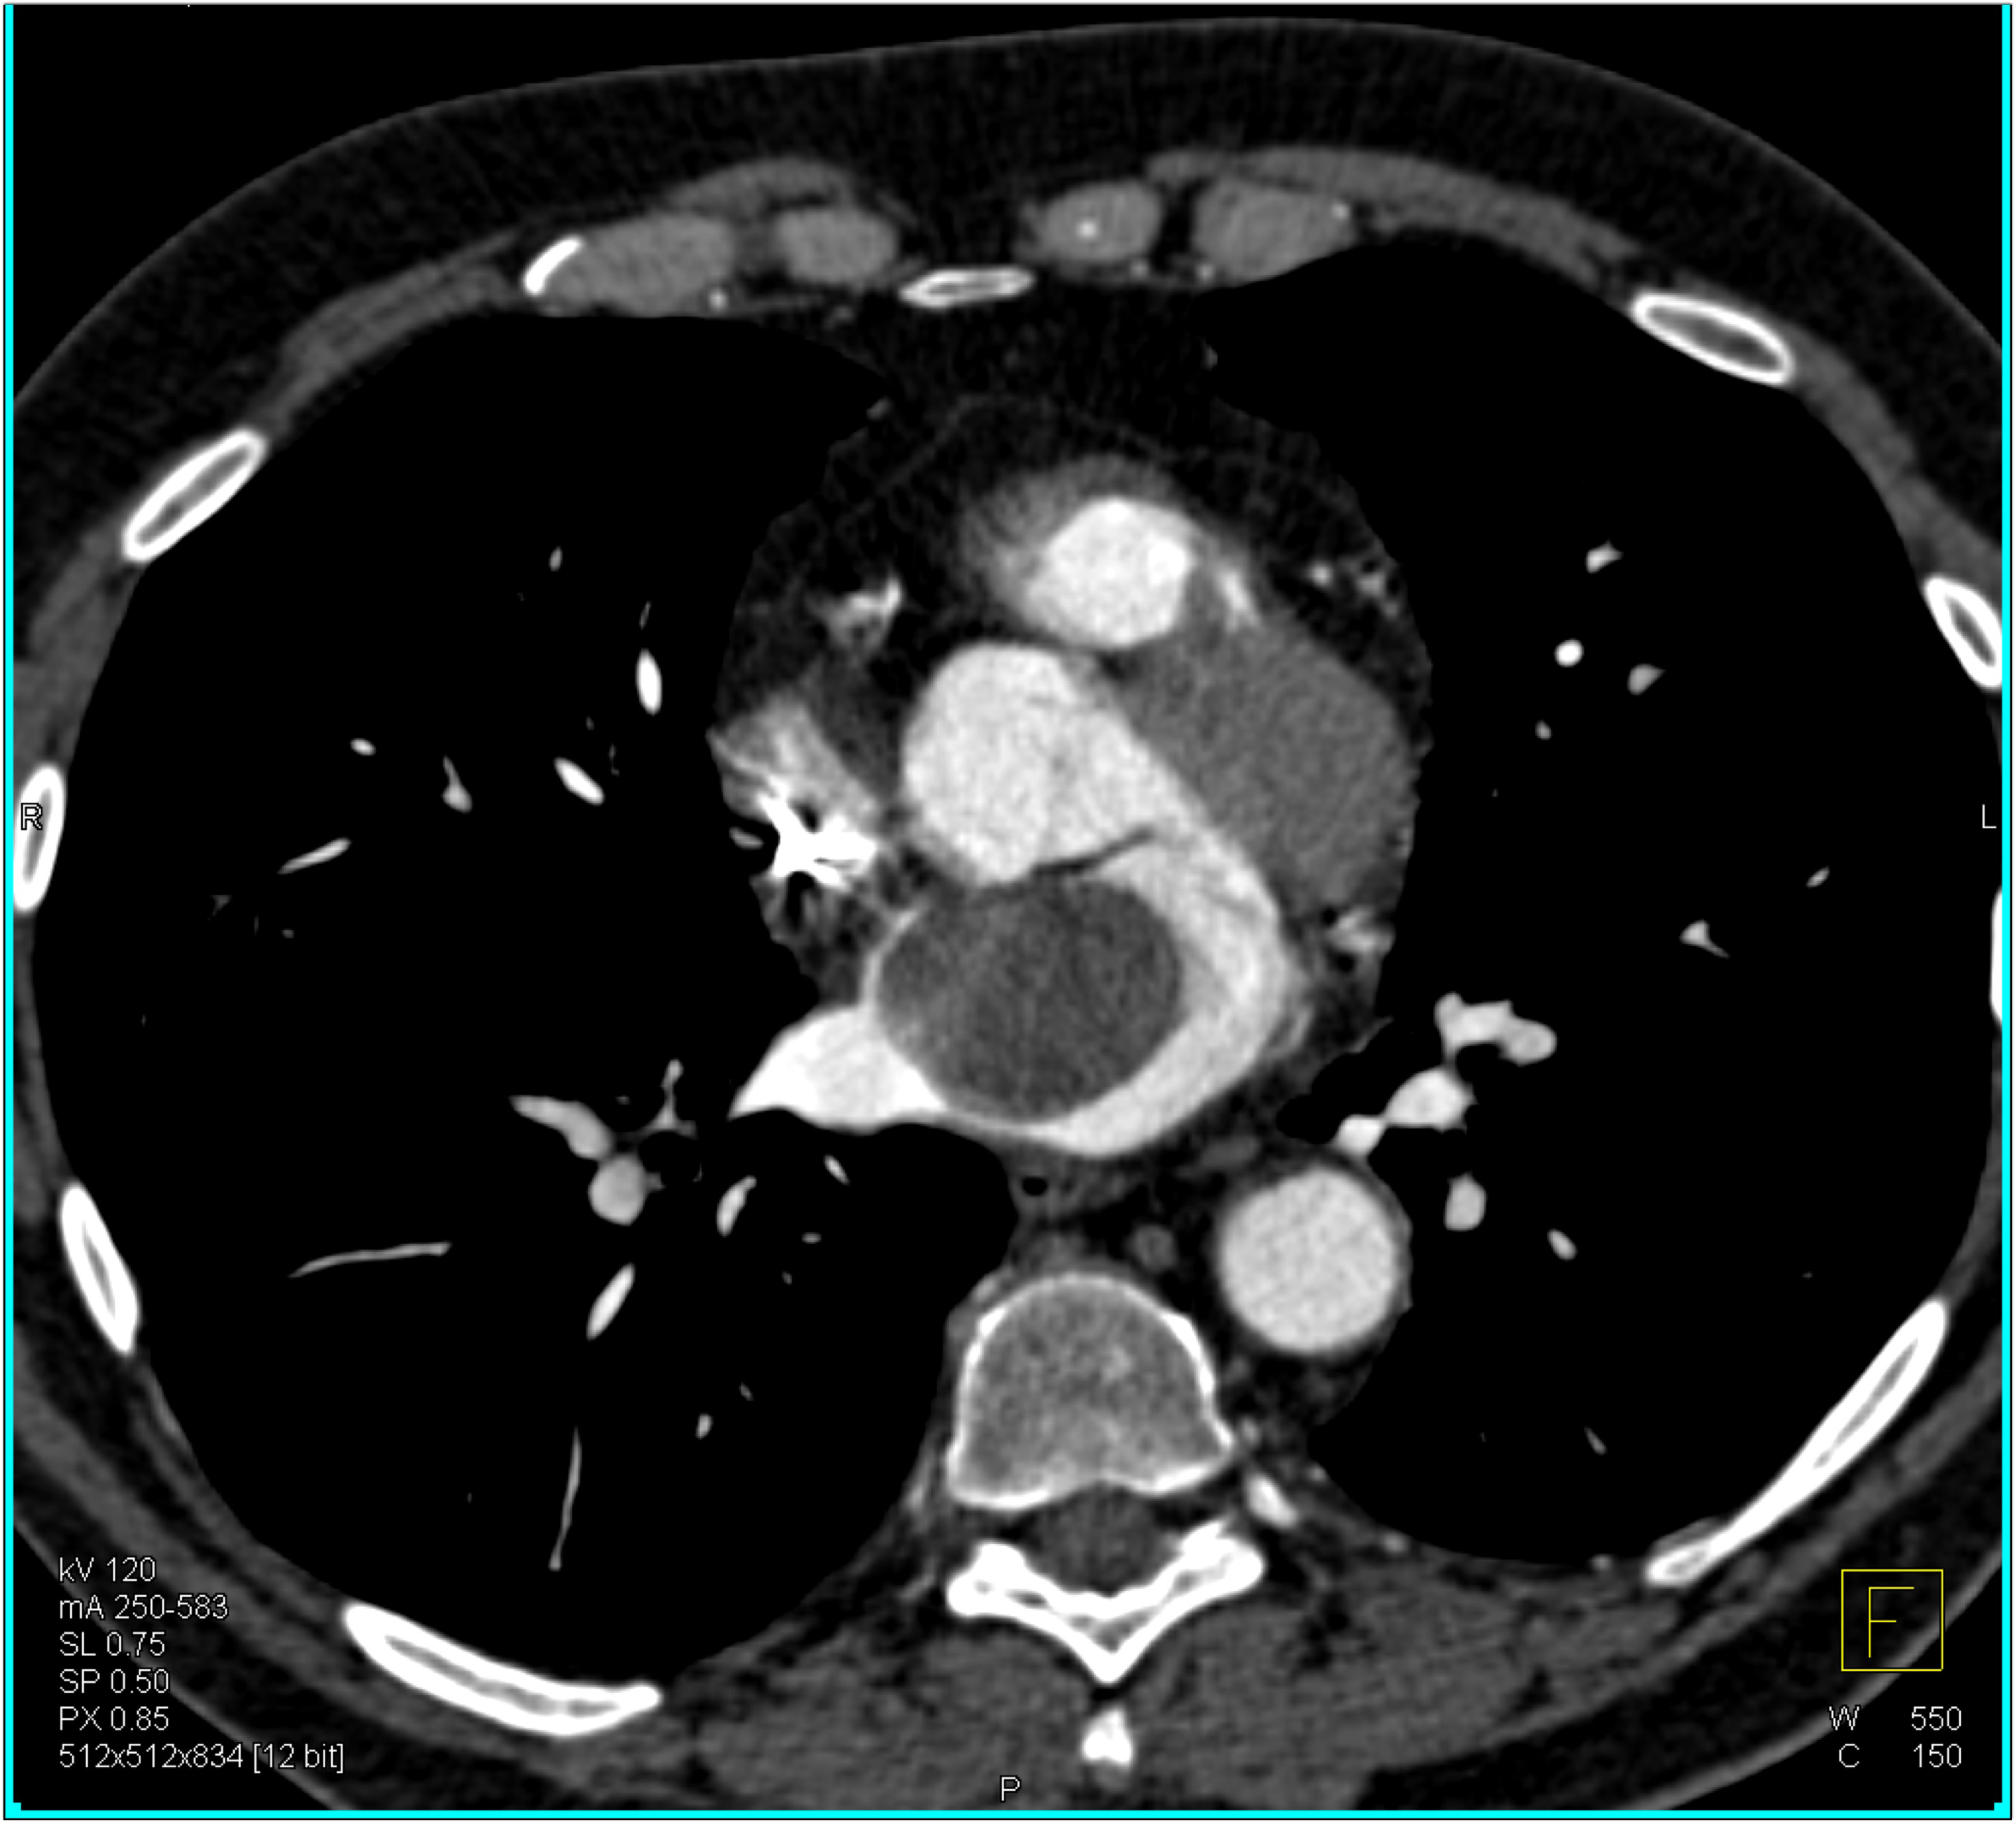

8) The most likely diagnosis in this case is?

atrial thrombus

metastatic disease to the left atrium

atrial myxoma

lymphoma